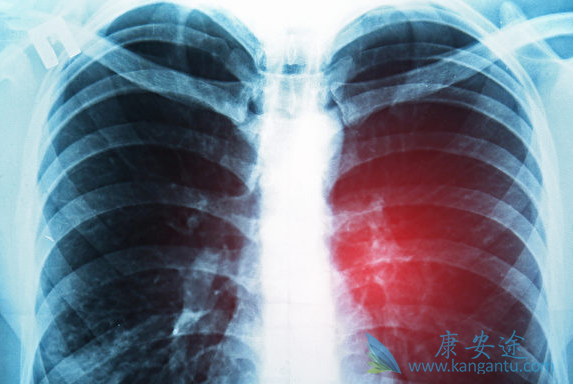

肺癌最好的治疗方法会根据病情发展有所改变

近些年来癌症疾病逐渐成为每年疾病中上升百分比例很快的疾病之一,常见的又胃癌,肠癌肺癌等,那么针对这些常见的疾病,在诊断过后,医生一般都采取哪些治疗方法帮助患者减轻病痛的折磨呢。下面小编详细的为大家介绍,肺癌最好的治疗方法是什么。

专家称对于肺癌的治疗主要是看患者的病情发展程度。我们将肺癌分早期、中期、晚期3个阶段。如果想要肺癌治愈,建议患者最好在肺癌早期的时候就开始抓紧治疗,这个阶段是肺癌能够治愈的关键节点,治疗难度并不是太大。

再次,专家称对于肺癌的治疗方法是非常重要的。一般来说,早期肺癌癌肿较小,未发生扩散转移,其最好的治疗方法为根治性手术切除。手术再结合一些中药术后调理的使用,双管齐下,康复的概率更高。如果是早期手术治疗比较好,如果是中后期放化疗治疗比较稳妥,所以说我们一定不能盲从,要根据自己的实际情况选择肺癌最好的治疗方法